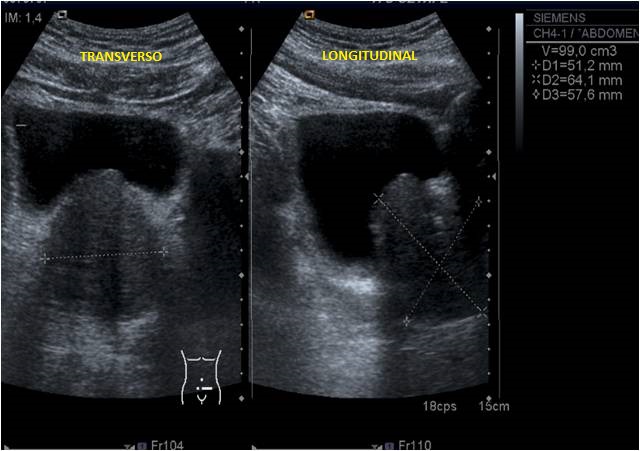

Perfecto, ahora que ya tenemos localizada la estructura hay que realizar dos cortes, transverso y longitudinal, de dicha glándula y haremos fotos de aquellos que lógicamente nos representen en la imagen la Próstata en su máximo tamaño, es decir, cortes centrales, no nos valen cortes periféricos de la estructura, ojo que en algunos pacientes, ésta será grande, pero en otros, será más pequeña y eso nos puede dificultar nuestra labor y tendremos que ser muy fino/as.

Los cortes serán estos:

Rojo: Transverso. Amarillo: Longitudinal SIEMPRE CON ANGULACIÓN.

El resultado será lo más parecido a esto:

En la imagen podemos ver, posterior a la Vejiga (anecoica), una estructura ovalada, hipoecogénica y homogénea, que es la Próstata, a la que le realizamos tres medidas para obtener un volumen:

• Derecha-Izquierda (Corte Transverso)

• Antero-Posterior (Corte Transverso)

• Cráneo-Caudal (Corte Longitudinal)

Estos tres cortes son indispensables para conseguir el volumen de la estructura, que previamente, en nuestro menú, habremos activado entrando en MEDIDAS y seleccionando la opción de VOLUMEN, que en cada casa comercial, será de una manera determinada.

Medidas y Volumen en cm3.